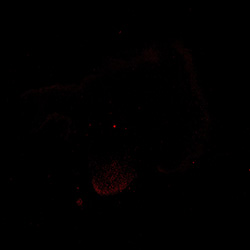

KI67

6PCW human midbrain